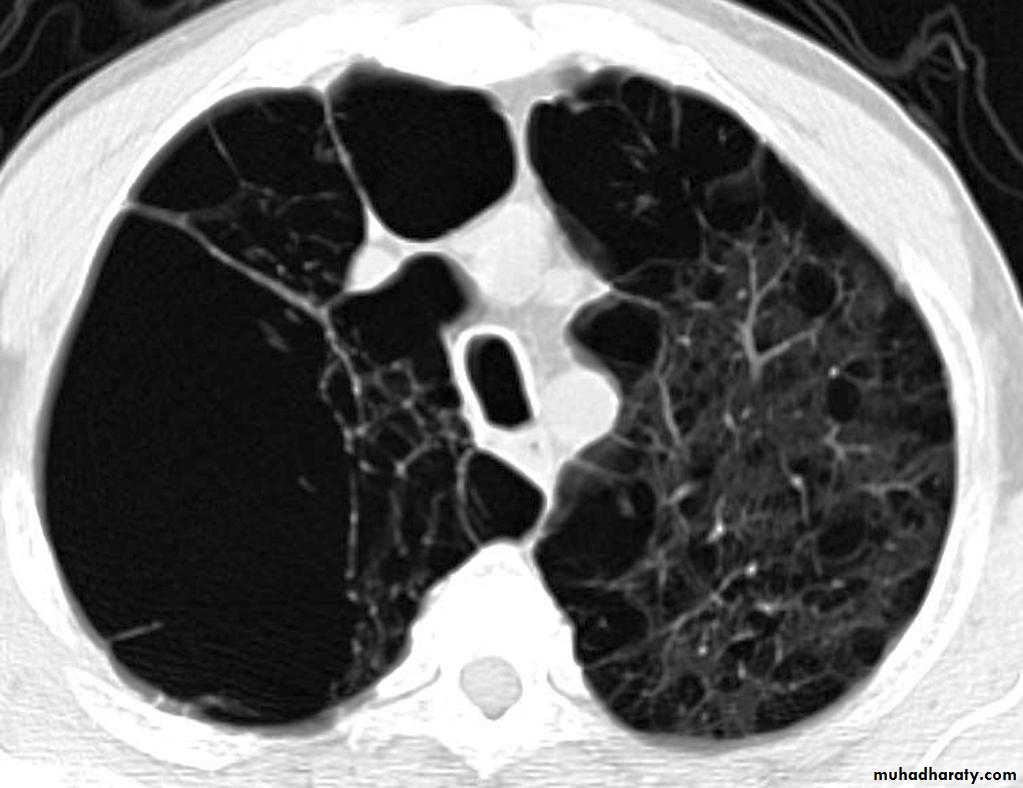

Bronchiectasis refers to abnormal dilatation of the bronchial tree and is seen in a variety of clinical settings. CT is the most accurate modality for diagnosis. It is largely considered irreversibleCauses of bronchiactasias very important to consider

Plain radiograph

Chest x-rays are usually abnormal1. Tram-track opacities are seen in cylindrical bronchiectasis, and

2. air-fluid levels may be seen in cystic bronchiectasis.

Honey comb shadow

3.Overall there appears to be an increase in bronchovascular markings, and bronchi seen end on may appear as ring shadows .

4.Pulmonary vasculature appears ill-defined, thought to represent peri bronchovascular fibrosis .